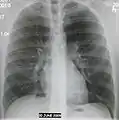

Normal AP CXR

Normal lateral CXR